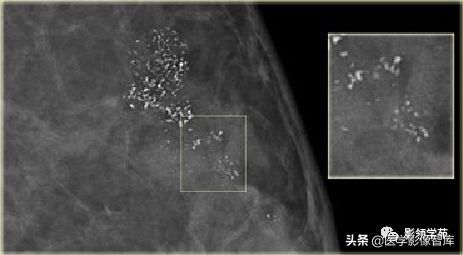

细小线样或细小分枝状

细小的线样或弯曲不规则钙化,通常<0.5mm,暗示管腔充填,如“铸形” 。通常为BI-RADS5

阶段性分布,其中有些呈线样分布 BI-RADS5

BI-RADS 5 活检证实高级DCIS

线状分布:沿导管方向线状分布:手术病理:浸润性导管癌。